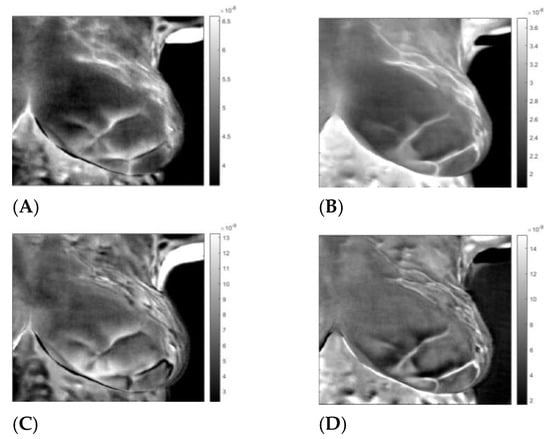

3. Results

3.3. Analysis